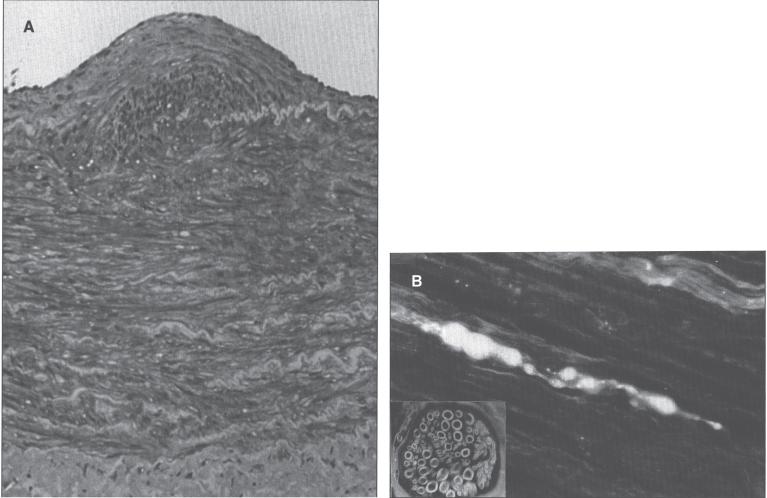

Trace elements are chemical elements needed in minute amounts for normal physiology. Some of the physiologically relevant trace elements include iodine, copper, iron, manganese, zinc, selenium, cobalt and molybdenum. Of these, some are metals, and in particular, transition metals. The different electron shells of an atom carry different energy levels, with those closest to the nucleus being lowest in energy. The number of electrons in the outermost shell determines the reactivity of such an atom. The electron shells are divided in sub-shells, and in particular the third shell has s, p and d sub-shells. Transition metals are strictly defined as elements whose atom has an incomplete d sub-shell. This incomplete d sub-shell makes them prone to chemical reactions, particularly redox reactions. Transition metals of biologic importance include copper, iron, manganese, cobalt and molybdenum. Zinc is not a transition metal, since it has a complete d sub-shell. Selenium, on the other hand, is strictly speaking a nonmetal, although given its chemical properties between those of metals and nonmetals, it is sometimes considered a metalloid. In this review, we summarize the current knowledge on the inborn errors of metal and metalloid metabolism.

微量元素是正常生理功能所需的微量化学元素。一些与生理相关的微量元素包括碘、铜、铁、锰、锌、硒、钴和钼。其中,有些是金属,特别是过渡金属。原子的不同电子壳层具有不同的能级,最靠近原子核的电子壳层能量最低。最外层电子的数量决定了该原子的反应活性。电子壳层又分为子壳层,特别是第三壳层有s、p和d子壳层。过渡金属被严格定义为原子具有不完全d子壳层的元素。这种不完全的d子壳层使它们易于发生化学反应,特别是氧化还原反应。具有生物学重要性的过渡金属包括铜、铁、锰、钴和钼。锌不是过渡金属,因为它有一个完整的d子壳层。另一方面,严格来说硒是一种非金属,尽管鉴于其化学性质介于金属和非金属之间,它有时被视为类金属。在本综述中,我们总结了目前关于金属和类金属代谢先天性缺陷的知识。